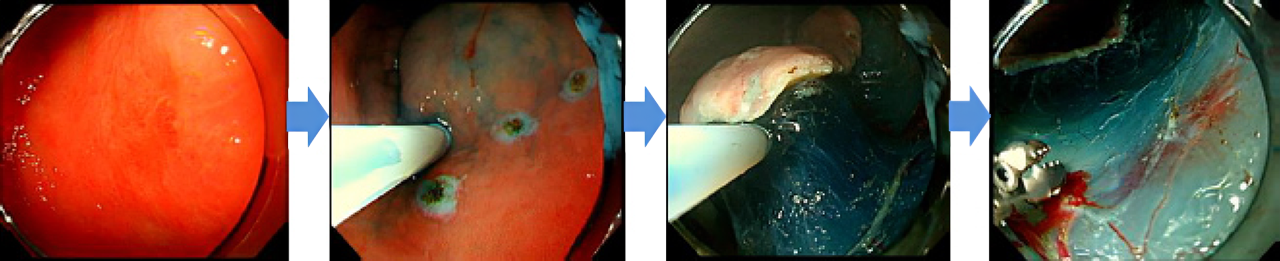

内視鏡画像で見る内視鏡的粘膜下層剥離術(ESD)

内視鏡の鉗子口から挿入した特殊なナイフを用いて病変の周囲を切開し、粘膜下層に生理食塩水を注射し、粘膜下層から「剝がし取る」治療法です。

内視鏡的粘膜下層剥離術(ESD)は、その内視鏡的治療の1つで内視鏡の鉗子口から挿入した特殊なナイフを用いて病変の周囲を切開し、粘膜下層から「剥がし取る」治療法です。これにより、大きな病変でも一括切除が可能となり、患者の治療負担の軽減や生活の質(QOL:Quality of life)の向上にも繋がります。